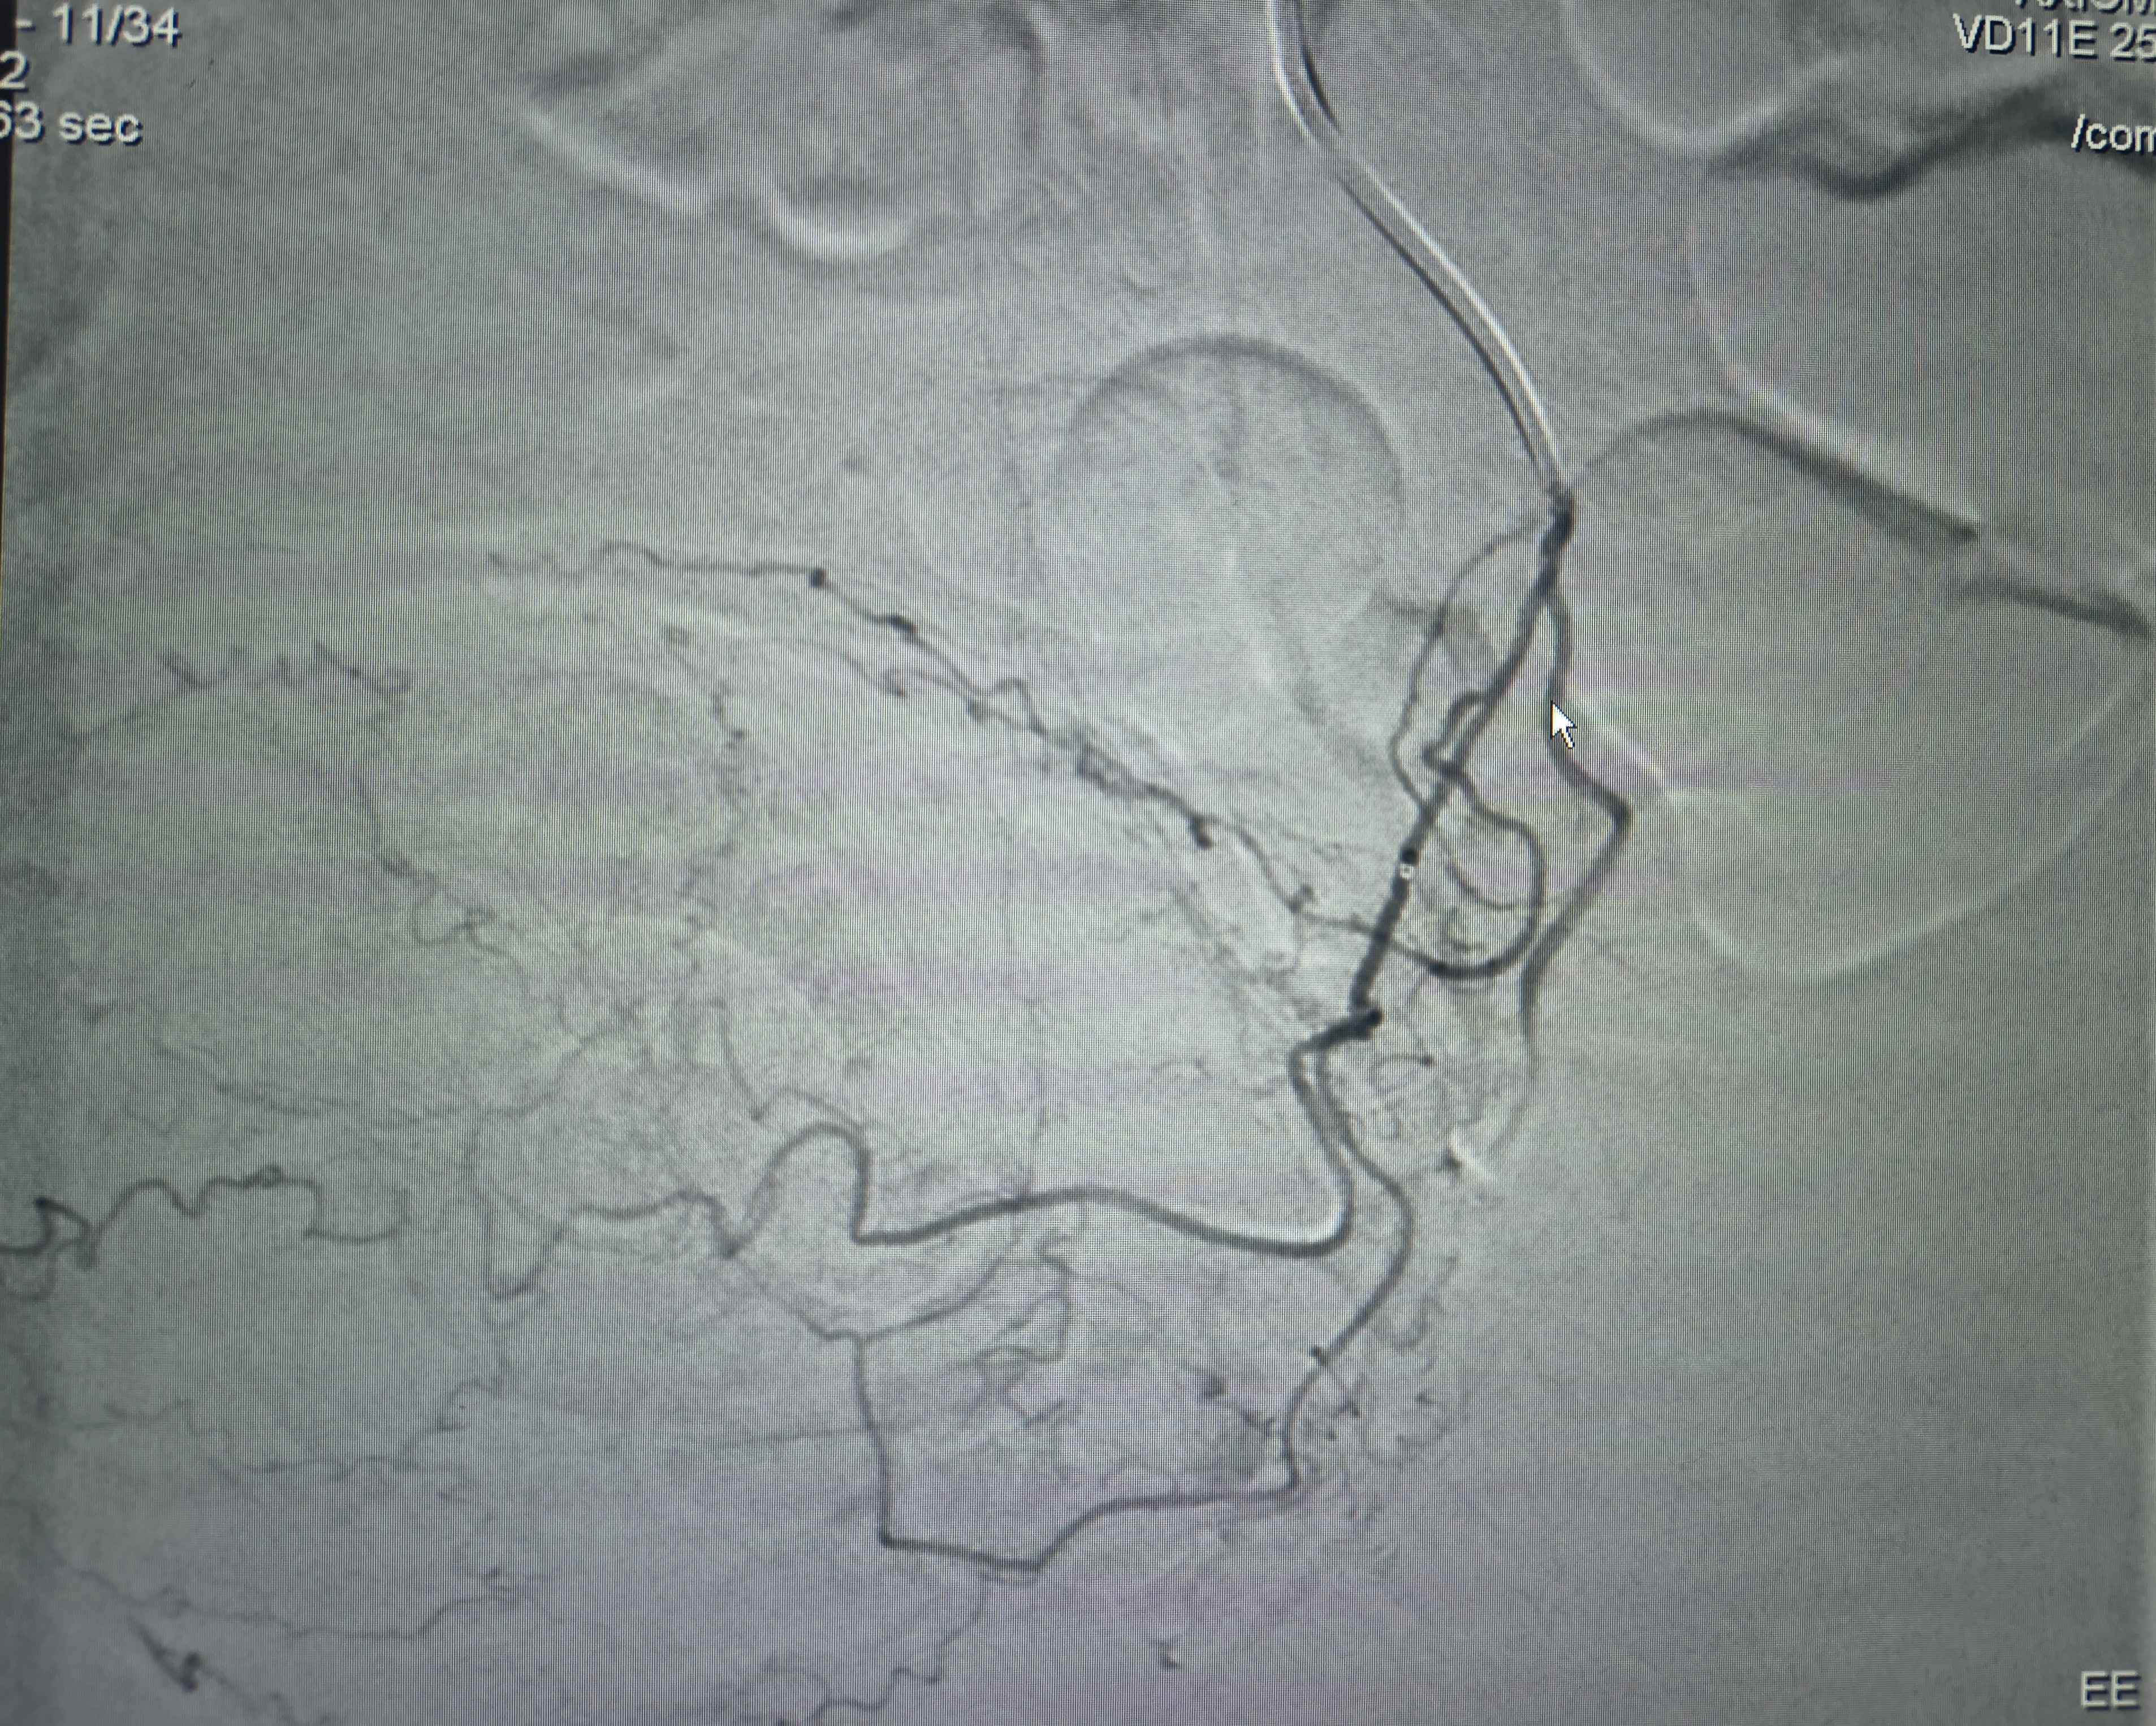

Prostate Artery Embolization

Prostate Artery Embolization: How Colonel Madhupreet Singh Found Relief at IRfacilities